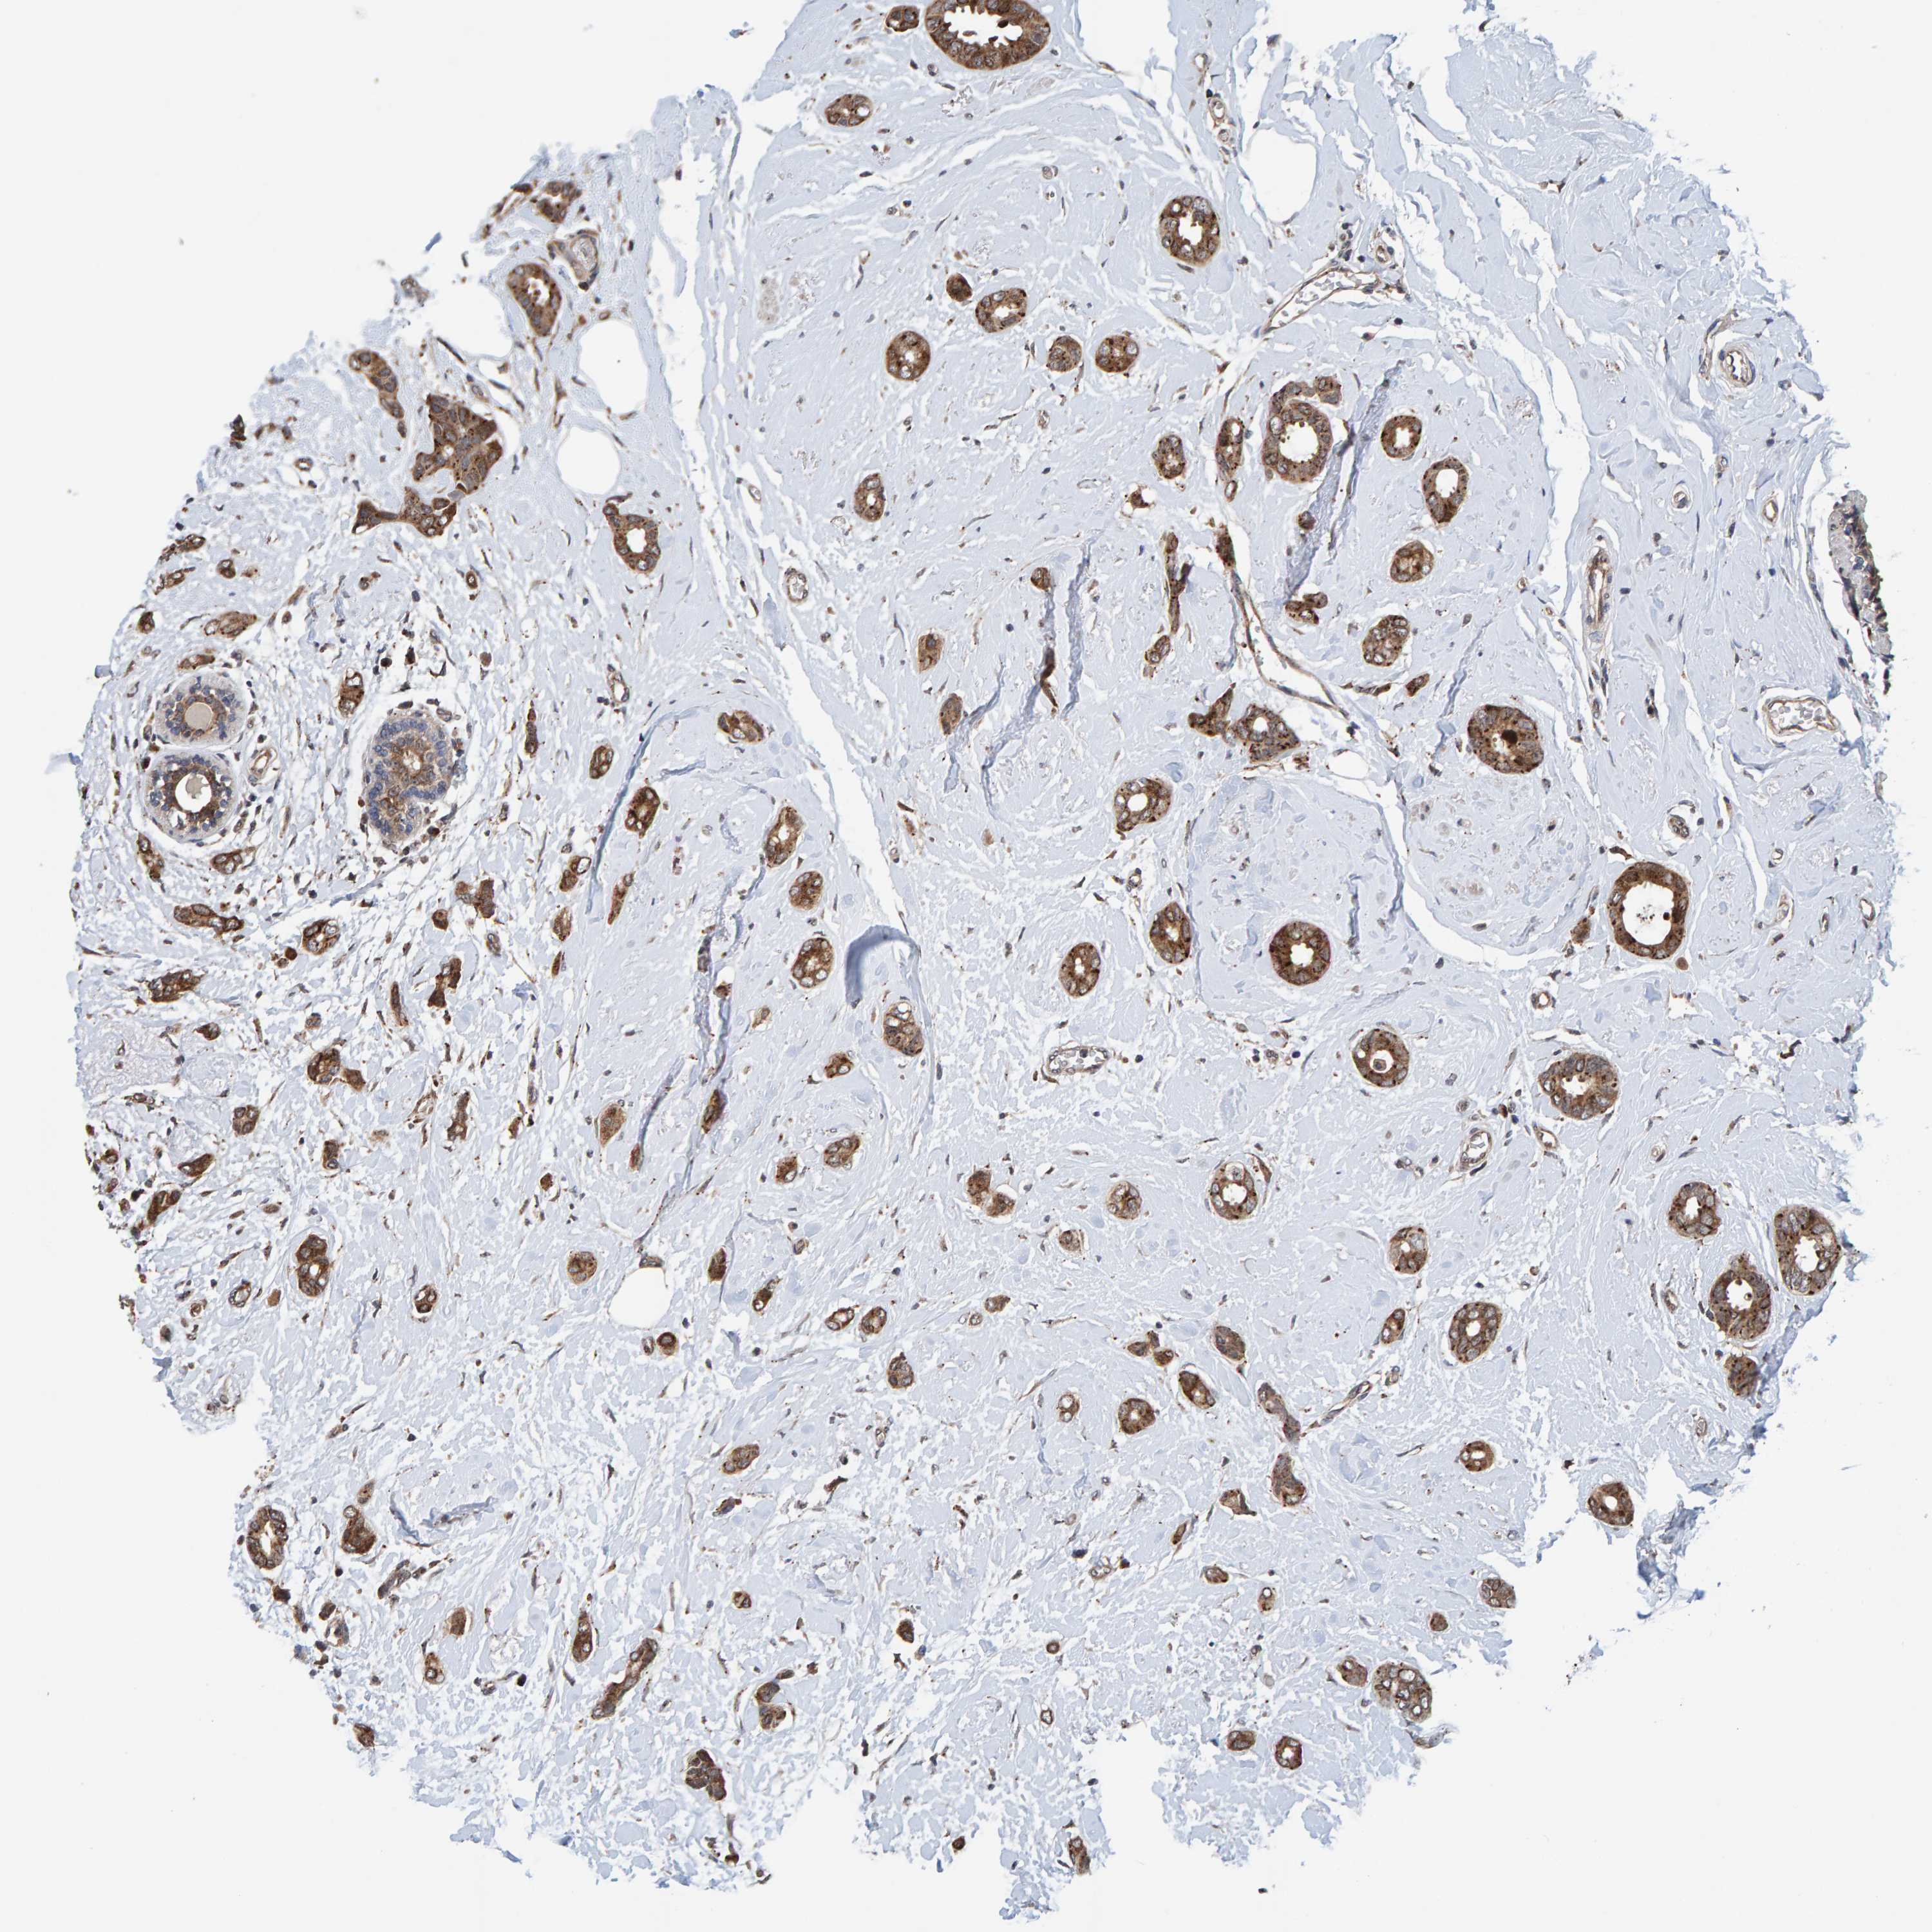

BRCA TCGA BRCA VALIDATION PROTEIN EXPRESSION

ANTIBODIES

AND

VALIDATION